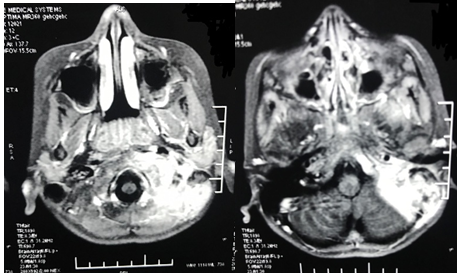

Patient was posted for immediate surgery under antibiotic cover. A left modified radical mastoidectomy was done. Peri-operatively granulations were seen in the middle ear along with soft tissue growth seen in external auditory canal and hypotympanum extending to mastoid cavity and eustachian tube. Infected left sigmoid sinus and internal jugular vein thrombus was evacuated (Figure 4a,4b ,4c). Intra-operative swabs collected for Acid fast bacilli, culture and sensitivity and Zeil-Nelson staining reported negative. Histopathology report of biopsy of middle ear granulations revealed multifocal epitheloid granulomas, multinucleate histiocytic giant cells and abundant lymphoplasma cell infiltrate with caseous necrosis (Figure 5). Postoperatively, patient was immediately started on antitubercular therapy in addition to adjunct treatment with cervical collar stabilization. Within two weeks of starting antitubercular therapy, patient showed remarkable recovery with disappearance of otologic complaints and relief of neck pain. Patient maintained regular 3-month follow-up which showed well epithelialized cavity with no recurrence.

Figure 5 Microscopy of biopsy from left middle ear granulations: Epitheloid granulomas, multinucleate histiocytic giant cells with caseous necrosis.